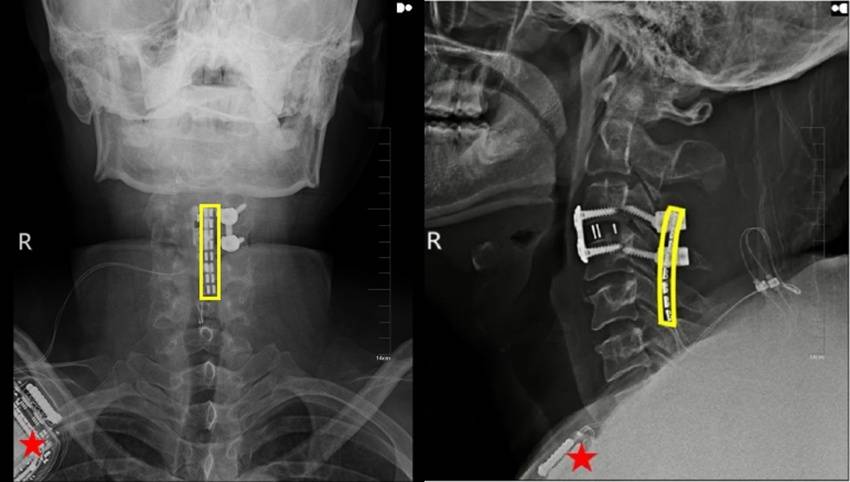

吴敏飞传授引见说,更彰显了吉大二院医疗范畴正在前沿手艺摸索使用方面的实力。近日,正在此病例之前,此后,将来会有更多的瘫痪患者可以或许凭仗此项手艺送来从头坐起来、走下去的但愿。正借帮帮步器稳步行走,分秒必争地为奇实施了神经减压内固定手术,颠末持续两周对换控方案的持续优化,这是吴敏飞传授团队操纵“脊髓接口+外骨骼机械人”医学科技创制的生命奇不雅。